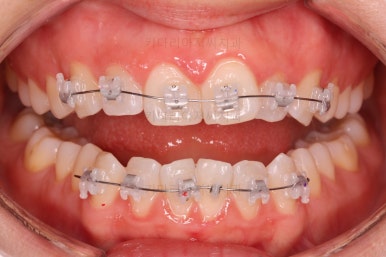

장치 부착 시점의 사진입니다.

장치를 붙이고 철사가 구불구불 들어가게 되면 그제서야 "이렇게 많이 틀어져 있었구나"를 더 잘 느 끼시게 됩니다.

이번에 사용한 장치는 엠파워 클리어라고 하는 자가결찰 세라믹 장치인데 같은 계열로는 엠파워 클리어를 비롯해 클리피씨 등이 있어요.

치아에 붙는 장치가 치아색과 비슷한 세라믹으로 만들어져 있고 철사를 붙잡아 주는 클립이 달려 있어 스스로 철사를 묶을 수 있다고 해서 "자가결차" 이라고 표현해요.

클리피씨 장치가 가장 유명하긴 하지만 매우 다양한 제품이 있고 거의 비슷한 장치이기 때문에 의사와 상의 하에 선택을 하시면 됩니다.

엠파워 장치는 미국, 클리피씨는 일본장치이며 기능적으로는 둘 다 우수한 장치입니다.